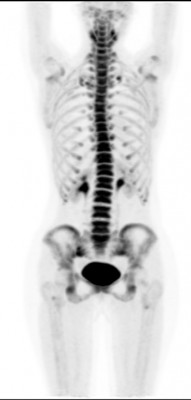

(рус) Позитронная эмиссионная томография (ПЭТ/КТ) всего тела с 18F-фторидом натрия